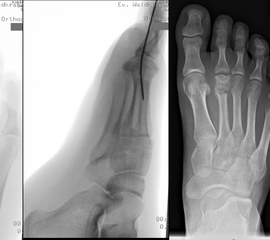

Calcaneus-Osteotomie

Die minimalinvasive Calcaneusverschiebeosteotomie bietet eindeutige Vorteile gegenüber dem offenen Verfahren, sodass wir bei Kindern und Jugendlichen nahezu keine offene Verschiebeosteotomie mehr durchführen. Am Calcaneus liegt die offene Wachstumsfuge dorsal. Bei der Durchführung müssen Schenkel der V-förmigen Osteotomie daher etwas steiler angelegt werden, in einem stumpfen Winkel (siehe Abb. 3 a-j). Für die Osteotomie liegen unsere Patienten auf dem Rücken und der BV wird für die exakte Seitaufnahme eingestellt. Der Fuß lagert auf einem hohen OP-Kissen und die Osteotomie kann bequem mit einem langen Kirschner-Draht und einem sterilen Stift angezeichnet werden (Abb. 15).

Abb. 15 a-b: Lagerung für die Calcaneus-Osteotomie minimalinvasiv.

Zum Lesen der Bildbeschreibung und zur Vollansicht bitte die Bilder anklicken. Bilder: A. Helmers.

Damit lässt sich im Verlauf Röntgenstrahlung für die jungen Patienten vermeiden und die minimalinvasive Osteotomie kann sicher durchgeführt werden. Anschließend erfolgt die Verschiebung oder Impaktion. Ist ein Gleiten nach plantar oder cranial des distalen Fragmentes erwünscht, wird die Osteotomie schräg ohne V-Form entweder verlängernd oder verkürzend durchgeführt (Abb. 16).